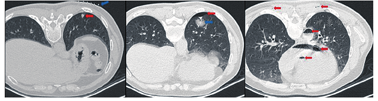

2018年11月采用胸腔镜下左下肺楔形切除术,视术中快速病理情况决定是否行根治性手术。患者取俯卧位,估计左下肺结节对应体表位置并放置显影定位板,行CT扫描确定进针位置、角度及深度(图1)。使用Hookwire(GALLINI S.R.L,意大利)进行穿刺并释放,再次行CT扫描确认结节和定位针位置,发现穿刺部位少量气胸,肺内有明显渗出(图2)。术毕患者诉头晕,恶心,双下肢不能活动,左上肢麻木,随即出现咯血。查体示神清,双下肢肌力0级,左上肢肌力3级,疼痛刺激均无感觉,右上肢活动和感觉正常。再次行CT扫描发现降主动脉及心腔内等处气体密度影(图3)。遂迅速转入我院ICU监护治疗,血压82/30 mmHg(1 mmHg=0.133 kPa),心率112次/min,T4以下感觉迟钝,较前减退,双下肢肌力0级,左上肢近端肌力2级,远端肌力3级,疼痛刺激无感觉,右上肢活动和感觉正常,双侧巴氏征未引出。查TnT升高、心电图提示T波高尖,查血气分析提示乳酸有升高趋势。予以积极升压维持组织灌注、营养神经、激素冲击、抗感染、营养支持等治疗。经过近1年的对症支持治疗及康复训练,患者生命体征平稳,双上肢活动和感觉正常,T7至膝盖浅感觉迟钝,膝盖以下浅感觉较弱,下肢肌力1级(左侧大腿可见肌肉收缩,右侧大腿、小腿均可见肌肉收缩,双侧脚趾可见轻微活动)。1年后患者复查胸部CT检查示患者左下肺结节较前变化不明显,定位针存留于左下肺内。经评估排除手术禁忌后,在胸腔镜下楔形切除左下肺结节并取出定位针,术中快速病理示浸润性非小细胞肺癌,遂加行左下肺切除+淋巴结清扫,术后病理示肺腺癌ⅢA(T1b,N2,cM0)。